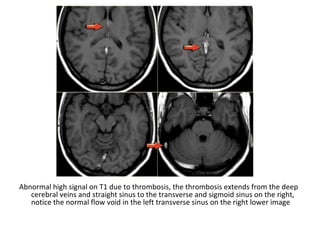

Abnormal high signal on T1 due to thrombosis, the thrombosis extends from the deep

cerebral veins and straight sinus to the transverse and sigmoid sinus on the right,

notice the normal flow void in the left transverse sinus on the right lower image